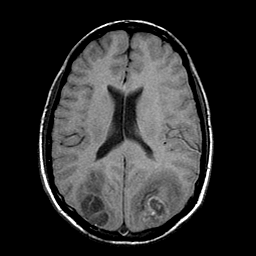

Sarcoma, MR Study #1 mr-t1 -- Slice #14

[Home][Help][Clinical] Slice 14